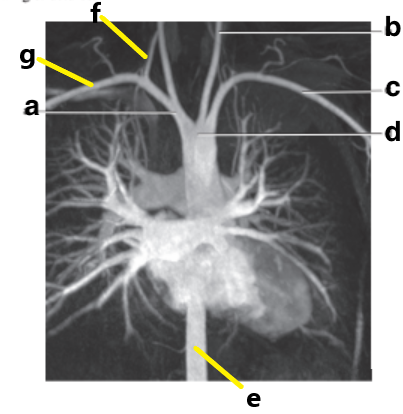

Which letter is the Left common carotid ?

b

Which letter is the left subclavian artery ?

Which letter is the Right common carotid artery ?

d

What is letter a ?

Brachiocephalic trunk

Which letter is the Descending aorta ?

f

c

Which letter is the right subclavian artery ?

g